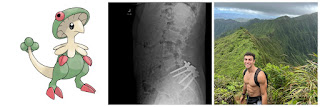

He did suffer a back injury and need surgery. He suffered the injury in Hawaii. Maybe his insurance didn't cover him because he was out of the state of residence on his insurance. That is his xray posted below after back surgery. I have an injury at same level. It is debilitating. He doesn't look as muscular as he used to look. He probably can't be as active as he was previously. An injury at that site makes it so you can't stand, walk, sit without pain. You could have sciatica besides pain and limited movement. For a young guy that's a big thing. He hadn't been in contact with friends and family for some months.